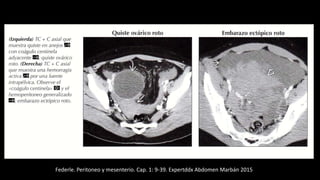

Federle. Peritoneo y mesenterio.

Cap. 1: 9-39. Expertddx Abdomen

Marbán 2015

Hemoperitoneo

Federle. Peritoneo y mesenterio. Cap. 1: 9-39. Expertddx Abdomen Marbán 2015

En la TC se ve una gran masa pélvica de partes

blandas (M), de densidad heterogénea,que

empuja la vejiga (V) hacia delante. El

diagnóstico en esta paciente con una historia

de traumatismo fue hemoperitoneo.

Paciente de 35 años con abdomen agudo. La TC con contraste muestra acumulación de fluido de

alta densidad compatible con hemoperitoneo por ruptura de aneurisma de la arteria esplénica.